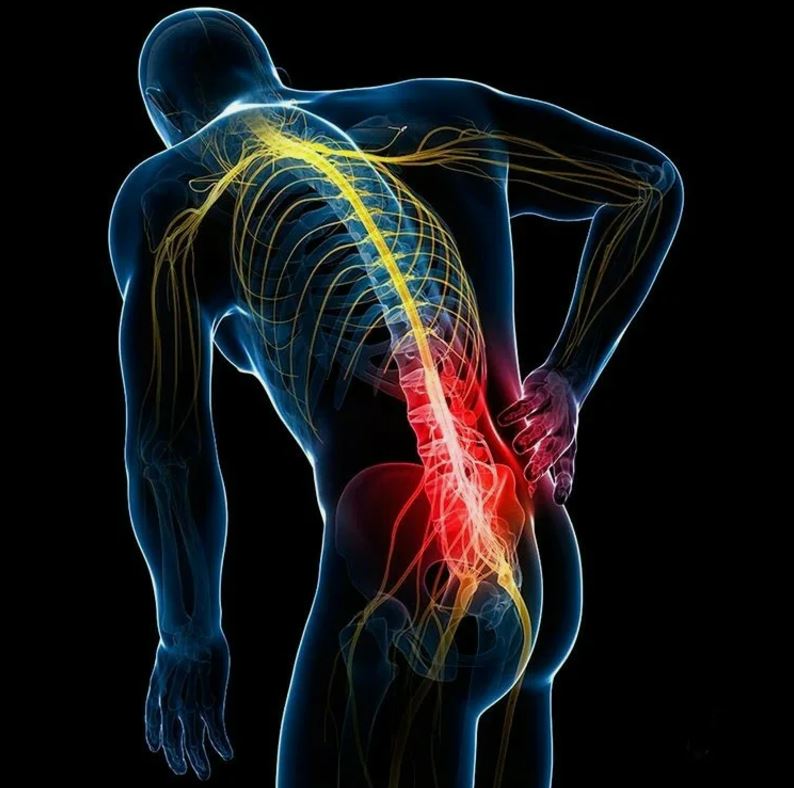

Думаю, что рассказывать разработчикам о том, как болит спина не стоит?

Столкнулся с этой проблемой если не каждый, то очень многие.

А причина банальная – мышцы “устают”, спина приобретает форму знака вопроса, происходит сдавливание межпозвонковых дисков и получаем привет от хронической боли в спине к 30-ти годам от пережатых нервных тканей.

Работа стоя, как оказалось, не снимает проблемы, а лишь переводит ее из области нижнего отдела позвоночника в область верхнего отдела.

Получаем боли в шее и плечах и дополнительные проблемы с венами.

Кстати, оказалось, что если от долгого сидения на стуле у вас возникает боль в ягодичной области или даже в ногах – это тоже пережатый нерв в спине в районе поясницы.

Предвестник более серьезных проблем с резкими скачкообразными болями от любого вашего движения.